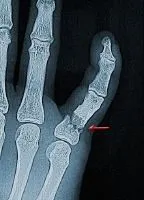

阿鬼癟嘴,左手捏著右手掌:「我手被門夾到了,好像骨折了」(´;ω;`)

右手來不及縮!手指被夾!到!了!還!斷!掉!了!

阿鬼在眾人爆笑下,無奈的講完了以上過程,急診主治笑到邊擦淚邊看X光:「嘿唷,學弟你還自我診斷正確捏,真的骨折了!」

阿鬼一臉哭喪:「因為我有聽到『啪』的一聲啊…」

還好骨科診斷不用開刀,石膏固定就好。緹娜整個啼笑皆非:「我真的服了你,你是知道我急診還缺石膏固定的個案數,來幫我充量的是不是?」

他倆人在石膏室內,緹娜一層一層摺疊好石膏布,浸水,上模,捆紗布跟繃帶,受傷的是右手小指頭,整個包成了翹小指樣子。